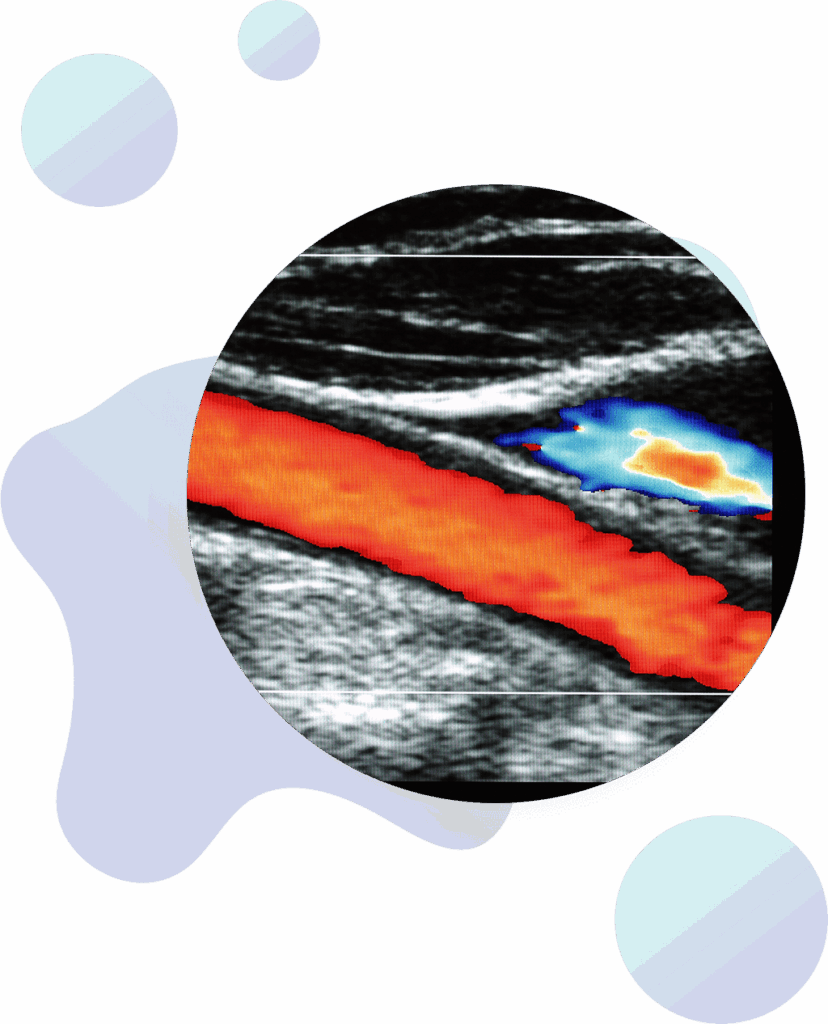

Carotid Doppler

Carotid Doppler is an ultrasound imaging technique that assesses the health of your carotid arteries –– two arteries on the sides of your neck that carry blood from your heart to your brain. If your test results are abnormal, your provider can recommend healthy lifestyle changes or medication to reduce your risk of a stroke.